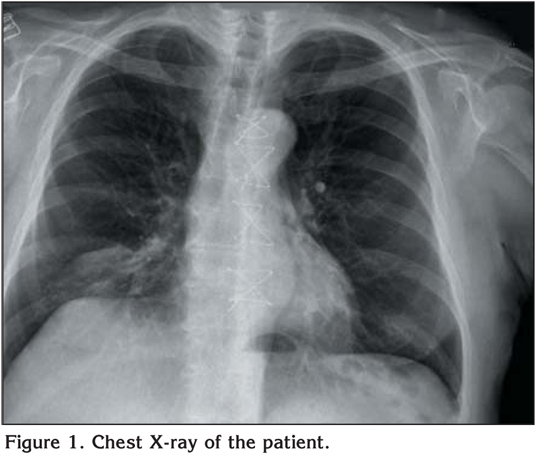

The admission chest X-ray revealed consolidation and atelectasis at basal part of the right lung (Figure 1).? Chest computed tomography (CT) demostrated pleural thickening, pleural effusion, and middle lobe lateral segment atelectasis of the right side suggesting bronchial obstruction (Figure 2).